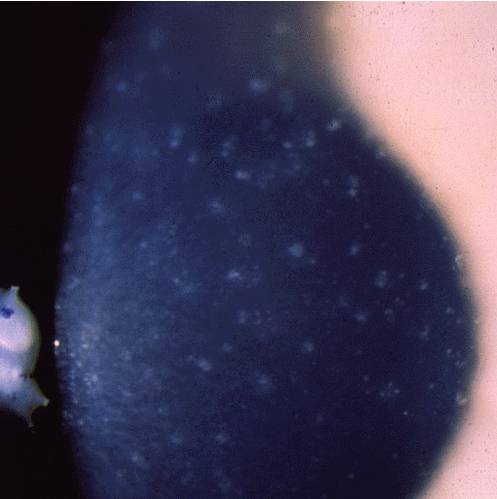

Макулярная (пятнистая) дистрофия роговицы. Имеет аутосомно-рецессивный тип наследования, ген CHST6 (сarbohydrate sulfotransferase 6 gene), локус 16q22. Морфологические изменения связаны с избыточным отложением в строме, эндотелии и десцеметовой мембране внутриклеточно и внеклеточно гликозаминогликанов. Заболевание проявляется в детском возрасте диффузным помутнением стромы, распространяющимся до лимба; позже обнаруживаются поверхностные центральные проминирующие неправильной формы белесые помутнения в виде пятен. В отличие от зернистой дистрофии, нет четких зон между помутнениями роговицы. В развитой стадии вовлекаются эндотелий и десцеметова мембрана, на которой обычно имеются каплевидные наложения — гутты. Позднее из-за эндотелиальной декомпенсации строма отекает и утолщается. К 20-30 годам острота зрения обычно значительно снижена, как и чувствительность роговицы, появляется светобоязнь. Из-за рецидивирующих эрозий возникают приступы боли.